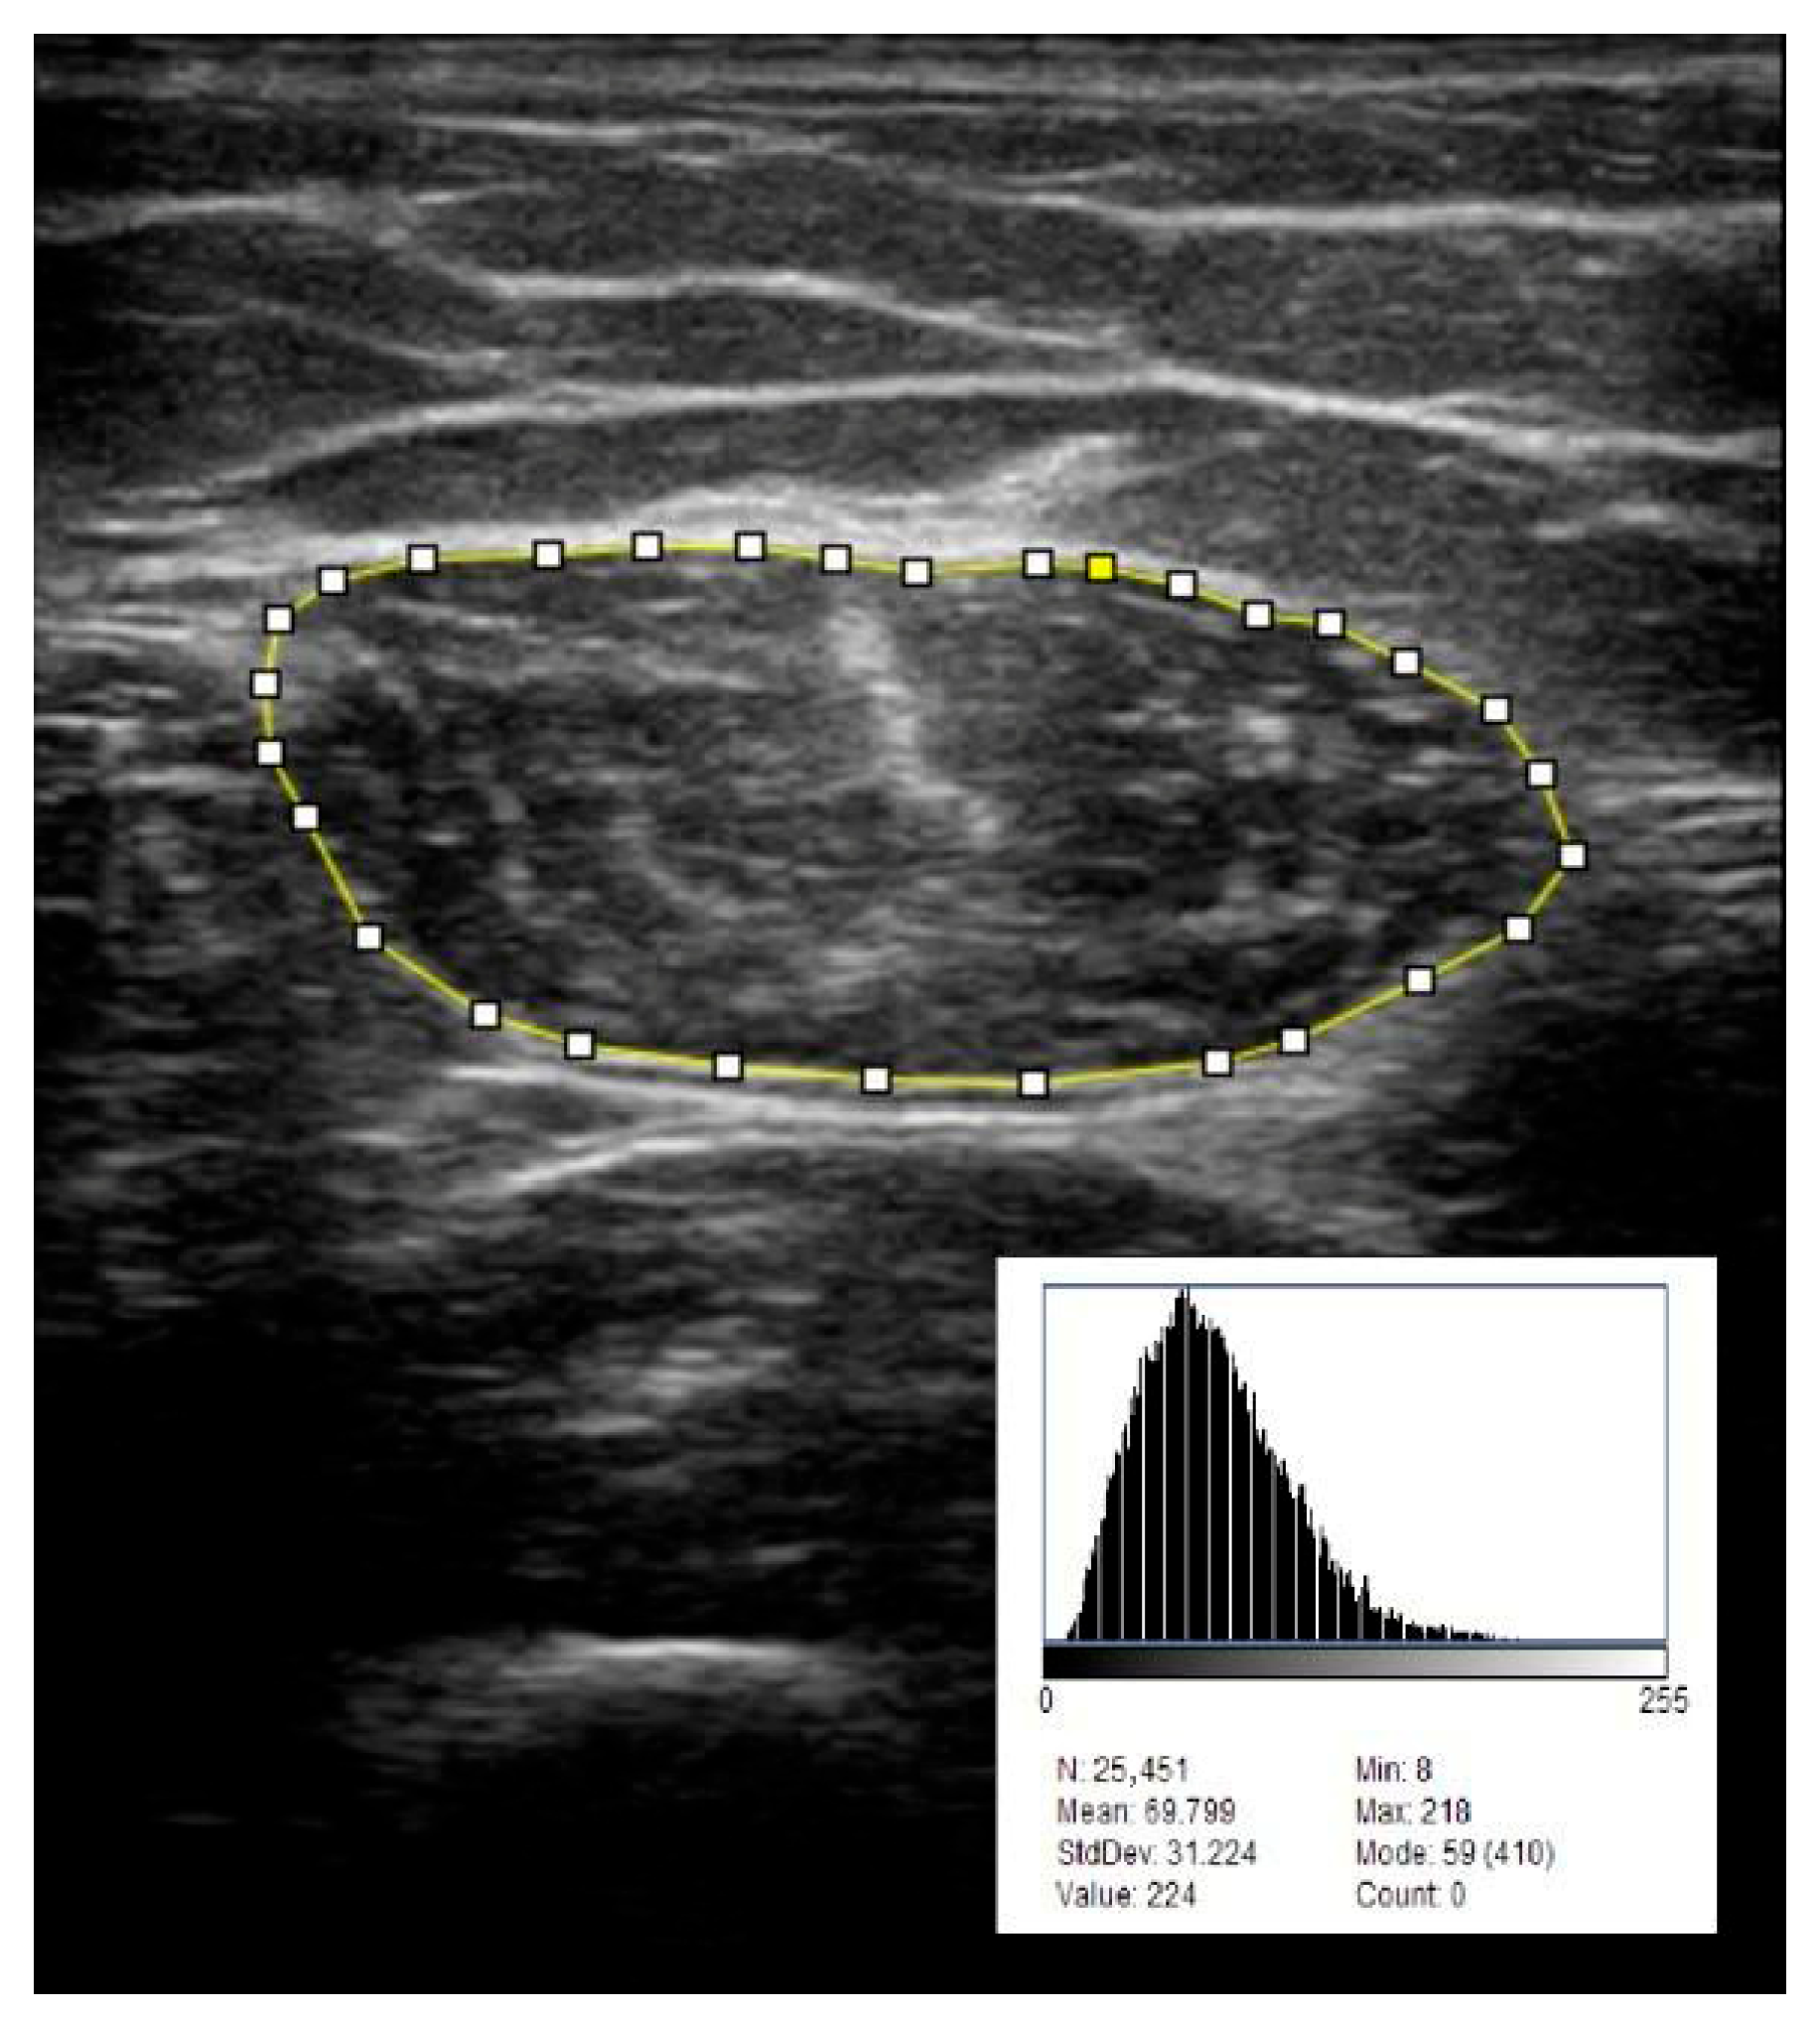

- Echo intensity (EI) was evaluated from transverse images captured at a fixed gain setting of 55%, using the ImageJ software (version 1.54g; National Institute of Health, Bethesda, MD, USA) as illustrated in Figure 1. Echo intensity values were expressed in grayscale units (0–255 scale). Echo intensity was evaluated in a subset of patients (n = 56).